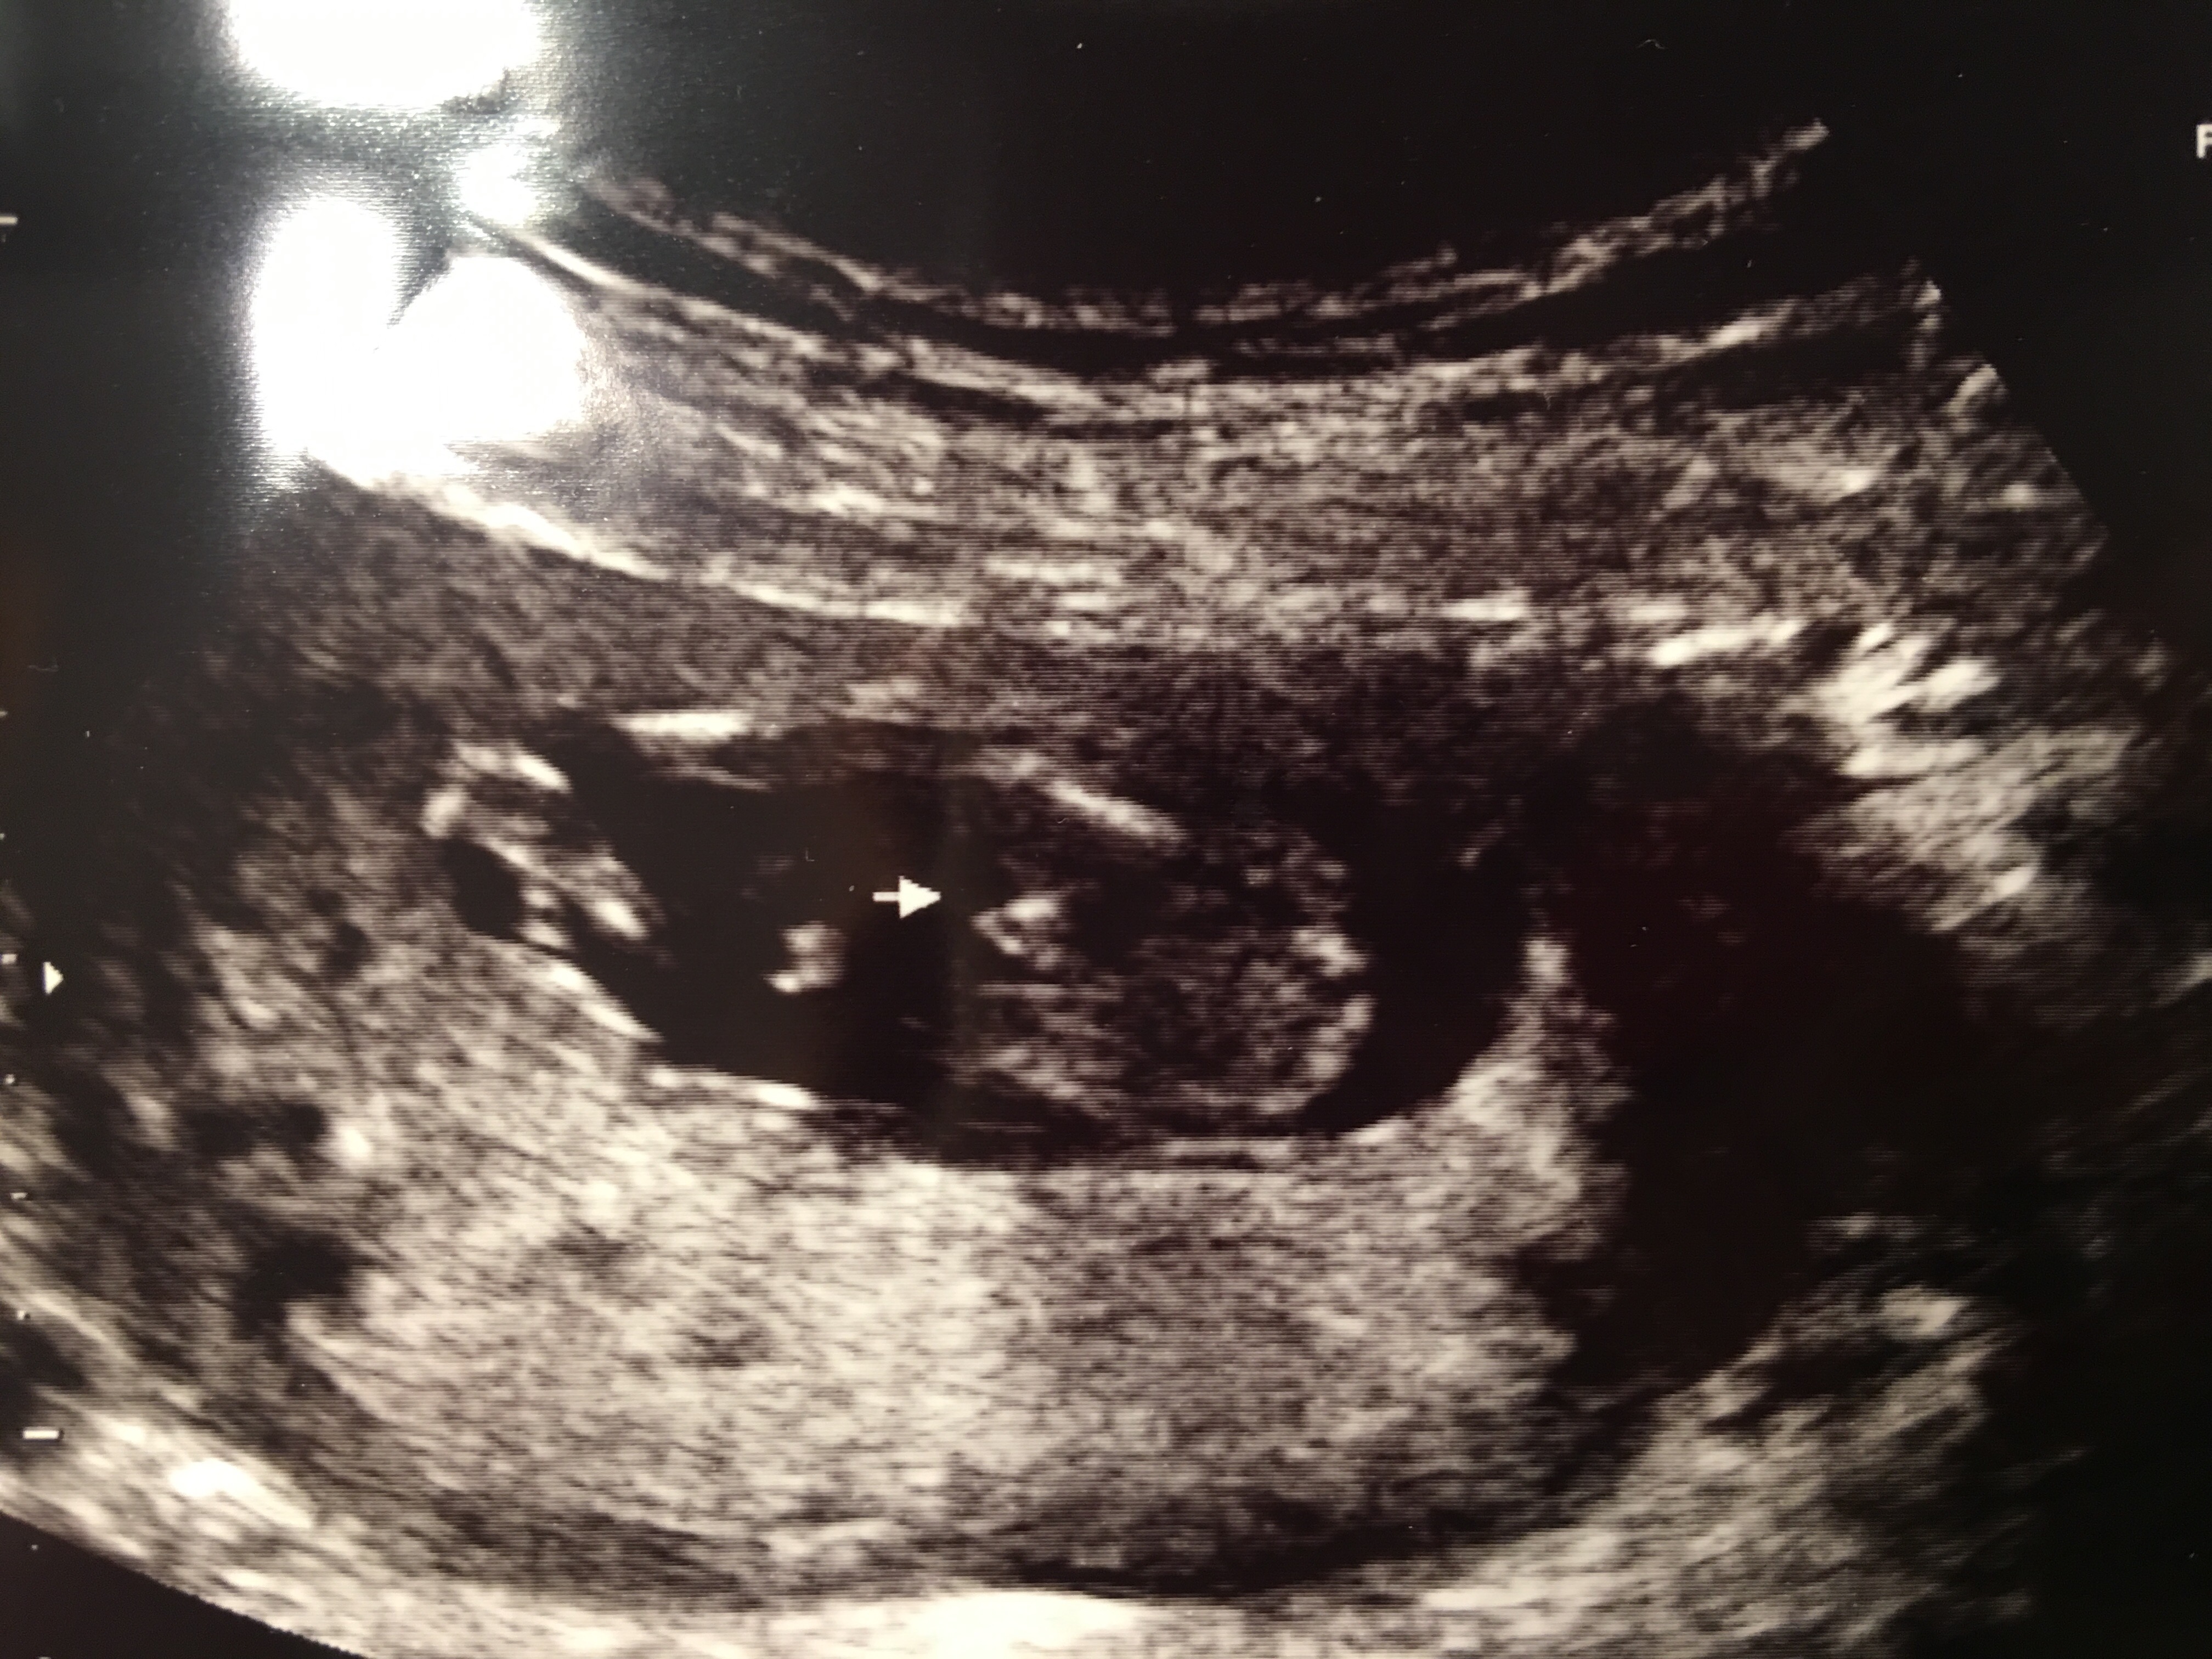

This is a potty shot from my 13 week 4 day ultrasound. Any guesses?!Attachment 34680Attachment 34680

I'm thinking boy :)